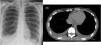

La radiografía de tórax en urgencias mostraba un pinzamiento de ambos senos costofrénicos compatible con derrame pleural bilateral (fig. 1A).

A. Radiografía de tórax AP al ingreso mostrando derrame pleural derecho y pinzamiento del seno costofrénico izquierdo. B. Tomografía axial computarizada torácica mostrando derrame pleural bilateral y derrame pericárdico (la flecha superior indica derrame pericárdico y la derecha, derrame pleural).

Una angio-tomografía computarizada de tórax (angio-TC) para descartar tromboembolismo pulmonar confirmó un moderado derrame pleural bilateral con atelectasias posterobasales y en el lóbulo medio (fig. 1B), que se confirmó con ecografía torácica, descartando afectación vascular.